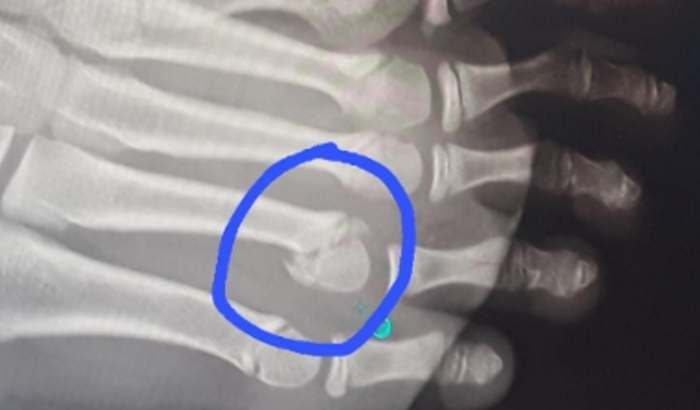

Meu nome é Nayra, sou mãe solteira e desde o mes passado estou sem poder trabalhar porque meu filho de 12 anos fraturou o pé. Estou aqui com muita humildade pedindo ajuda somente para alimentos🙌 qualquer valor para que eu possa comprar 2 cestas basicas pois sei que de pouco em pouco Deus abençoa🙌 Gratidao a qualquer um q puder ajudar🙌🙌